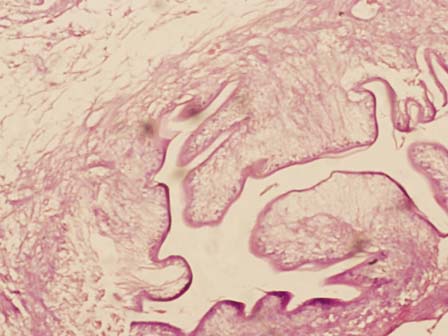

A 22 years old female presented with a soft tissue swelling in the floor of mouth. Examination revealed a soft cystic 1.5 cm swelling in the floor of mouth, rest of the oral cavity and the neck was normal. With a clinical diagnosis of a minor salivary gland tumor or a mucus retention cyst, patient underwent wide local excision of the swelling in order to make it the definitive surgery. The histology of the resected specimen showed the swelling to be a cysticercus (Figure 1). The patient was prescribed Albendazole for 18 months, and is well on follow-up.

Figure 1: Photomicrograph showing cysticercosis